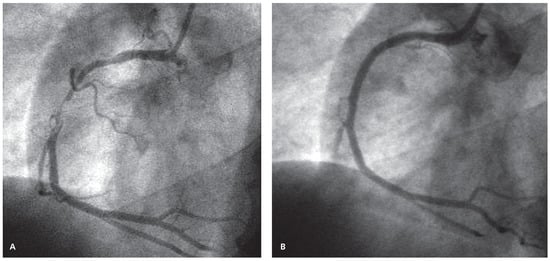

Case report A 22-year-old male experienced a presyncopal spell while studying for a university examination [...]